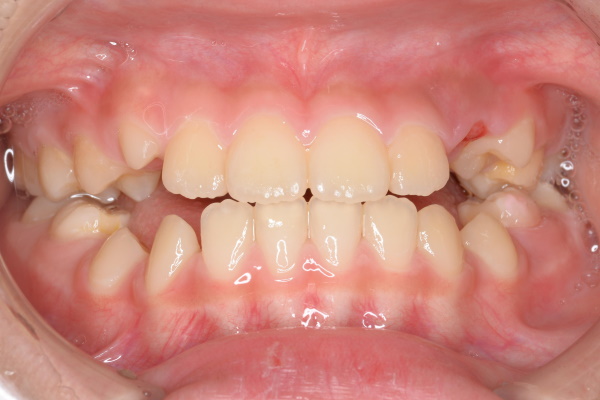

| 年齢・性別 | 7歳女児 |

| 治療期間 | 1年3か月 |

| 抜歯 | なし |

| 治療費 | 37万円(調整費、保定費まで含む総額制) |

| 備考 | インビザラインファースト |

| リスク・副作用 | 痛み・治療後の後戻り・歯根吸収・歯髄壊死・歯肉退縮 |